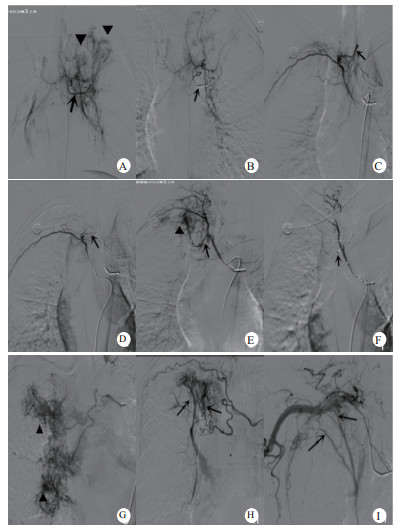

| 图A-F支气管扩张伴咯血患者图A箭头示左侧支气管动脉主干,三角示造影剂渗出外溢,提示局部有出血。图B采用复合栓塞,箭头示近端栓塞弹簧圈显影,血管呈“残根样”改变。图C箭头示异位支气管动脉与肋间动脉共干。图D箭头示近端栓塞弹簧圈,血管呈“残根样”改变。图E箭头示右上另一支气管动脉与后肋间动脉共干,三角示远端有造影剂渗出。图F箭头示近端栓塞弹簧圈显影,血管呈“残根样”改变,随访2年半,患者无复发出血。图G三角示造影剂浓聚渗出明显,提示出血范围较大。图H右侧支气管动脉-右上肺动脉瘘,该例患者行BAE,即刻止血失败后转胸外科行肺叶切除。图I右侧锁骨下动脉分支参与肺尖部供血,箭头示右侧锁骨下动脉-肺动脉瘘 图 1 术中造影情况 |